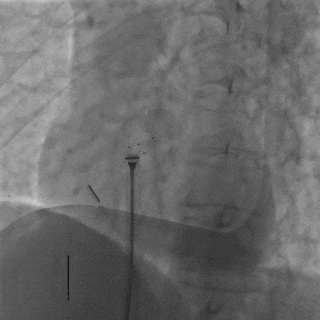

前顶钢缆和鞘管,牵拉成型线进行锁定,DSA下可见4个Mark点聚拢

牵拉试验

DSA下后退鞘管,轻轻牵拉钢缆,4个Mark点相对位置未发生变化,证明锁定成功

DSA下可见4个Mark点相对位置保持不变,整体随心博移动